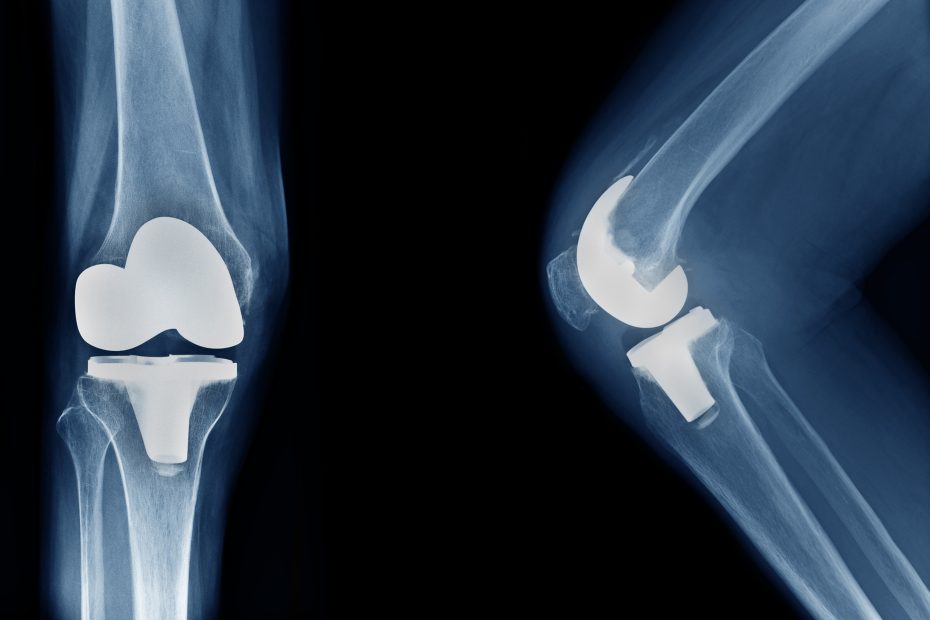

Starke Abnützungserscheinungen im Kniegelenk führen zur Kniegelenksarthrose oder Gonarthrose. Dieser Zustand kann zu starken Schmerzen, Bewegungseinschränkungen oder einer Verschlechterung der Lebensqualität führen. Eine gewisse Normalität… Mehr lesen »Wiederaufnahme des Sports nach Teilknie- und Vollknie-Ersatz: Fokus auf Skisport